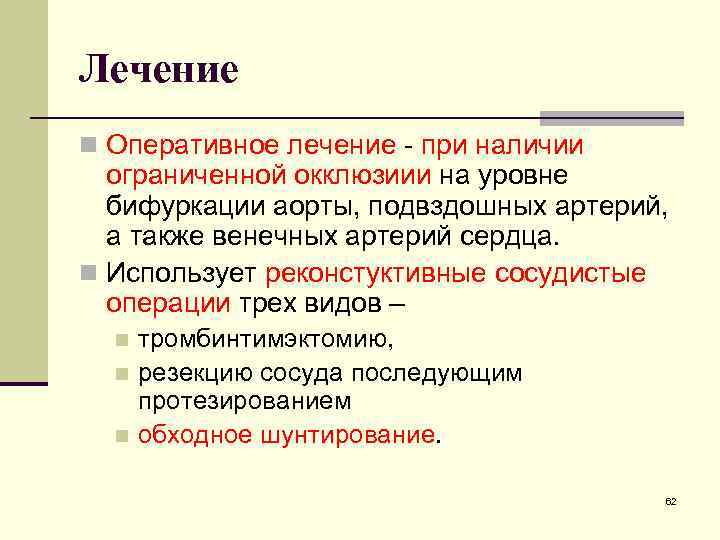

Лечение n Оперативное лечение - при наличии ограниченной окклюзиии на уровне бифуркации аорты, подвздошных артерий, а также венечных артерий сердца. n Использует реконстуктивные сосудистые операции трех видов – тромбинтимэктомию, n резекцию сосуда последующим протезированием n обходное шунтирование. n 62